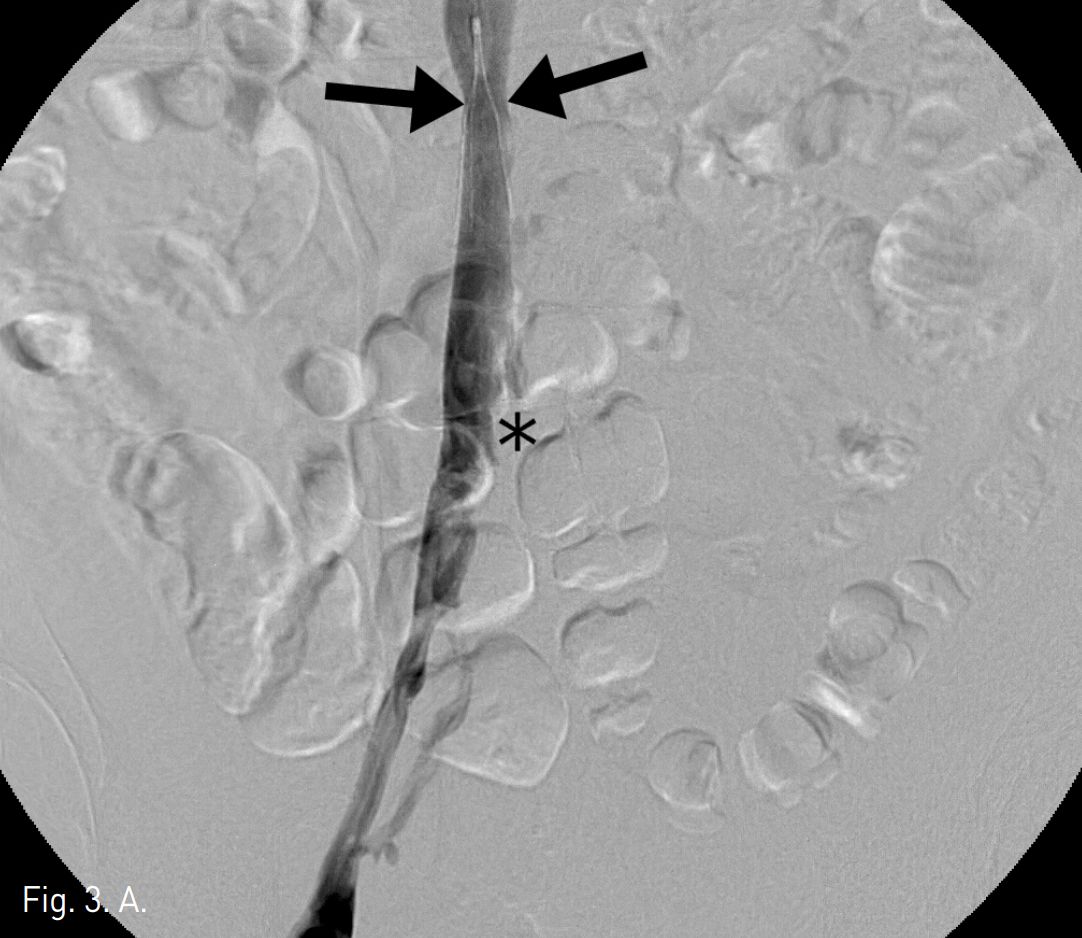

Fig. 3

Right (A) and left (B) iliac venograms obtained after catheter-directed thrombolysis and aspiration thrombectomy show restored IVC and iliac venous flow with small amount of residual thrombi (asterisks). There is a focal constriction of IVC lumen around the previous filter (arrows in A).